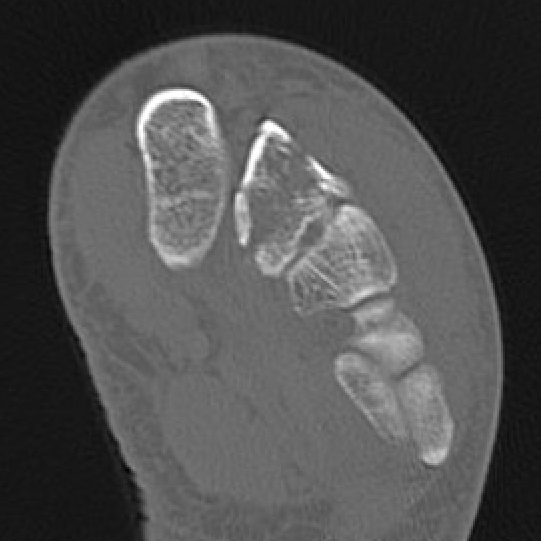

CT

Bone Scan / MRI

Show increased activity prior to xray changes